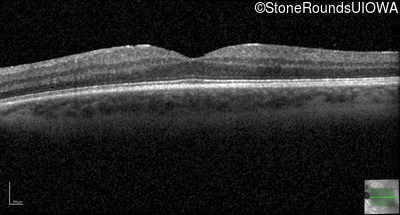

Optical Coherence Tomography - Right - 20/20

Exemplar / OCT Stack